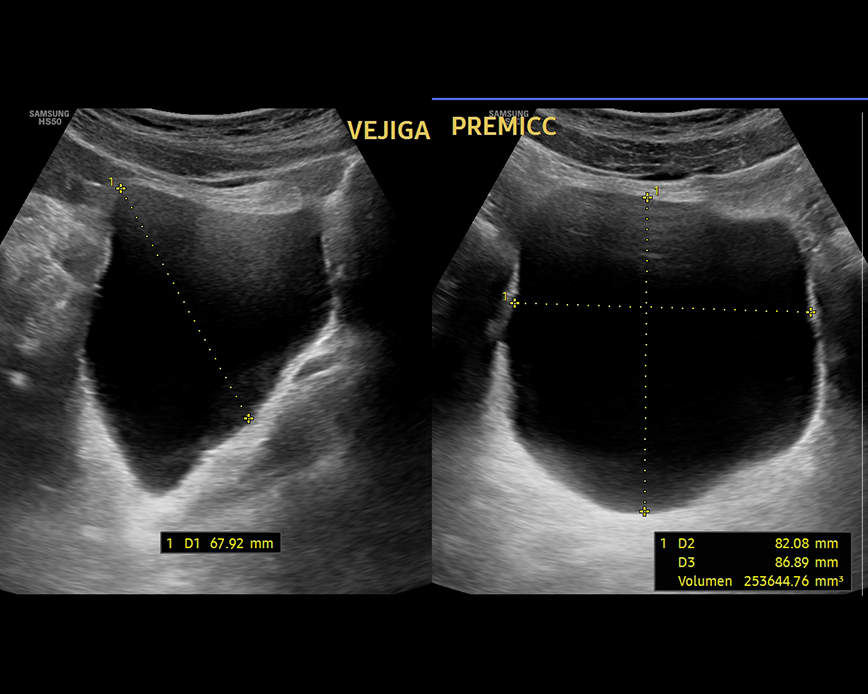

Ecografía Abdomen superior

- Estudio de la vesicular biliar y vías biliares